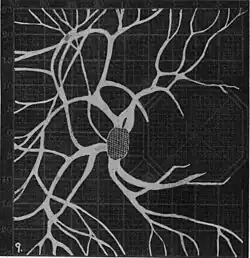

In the 1940s there were further developments. Evans reviewed the state of research in 1942.[6] In 1945, Welt designed a portable campimeter and linked the size of both the blind spot and the angioscotoma to retinal arterial pressure.[7] In the same year, Weekers and Humblet published detailed tracings that overlaid vessel photographs onto Bjerrum screen plots, firmly establishing the one‑to‑one correspondence between vascular anatomy and scotoma shape.[8]

20. Venous engorgement. 21. After pressure over internal 22. Same case, normal. 23. Scotoma after ligation of common carotid. 24. Edematous swelling of nerve and retina. 25, Normal blind spot of other eye. -

Widening of angioscotoma under various conditions (holding head lower than trunk; holding the breath; making digital pressure on the same eye; (a vein) on opposite eye; (an artery) on opposite eye).